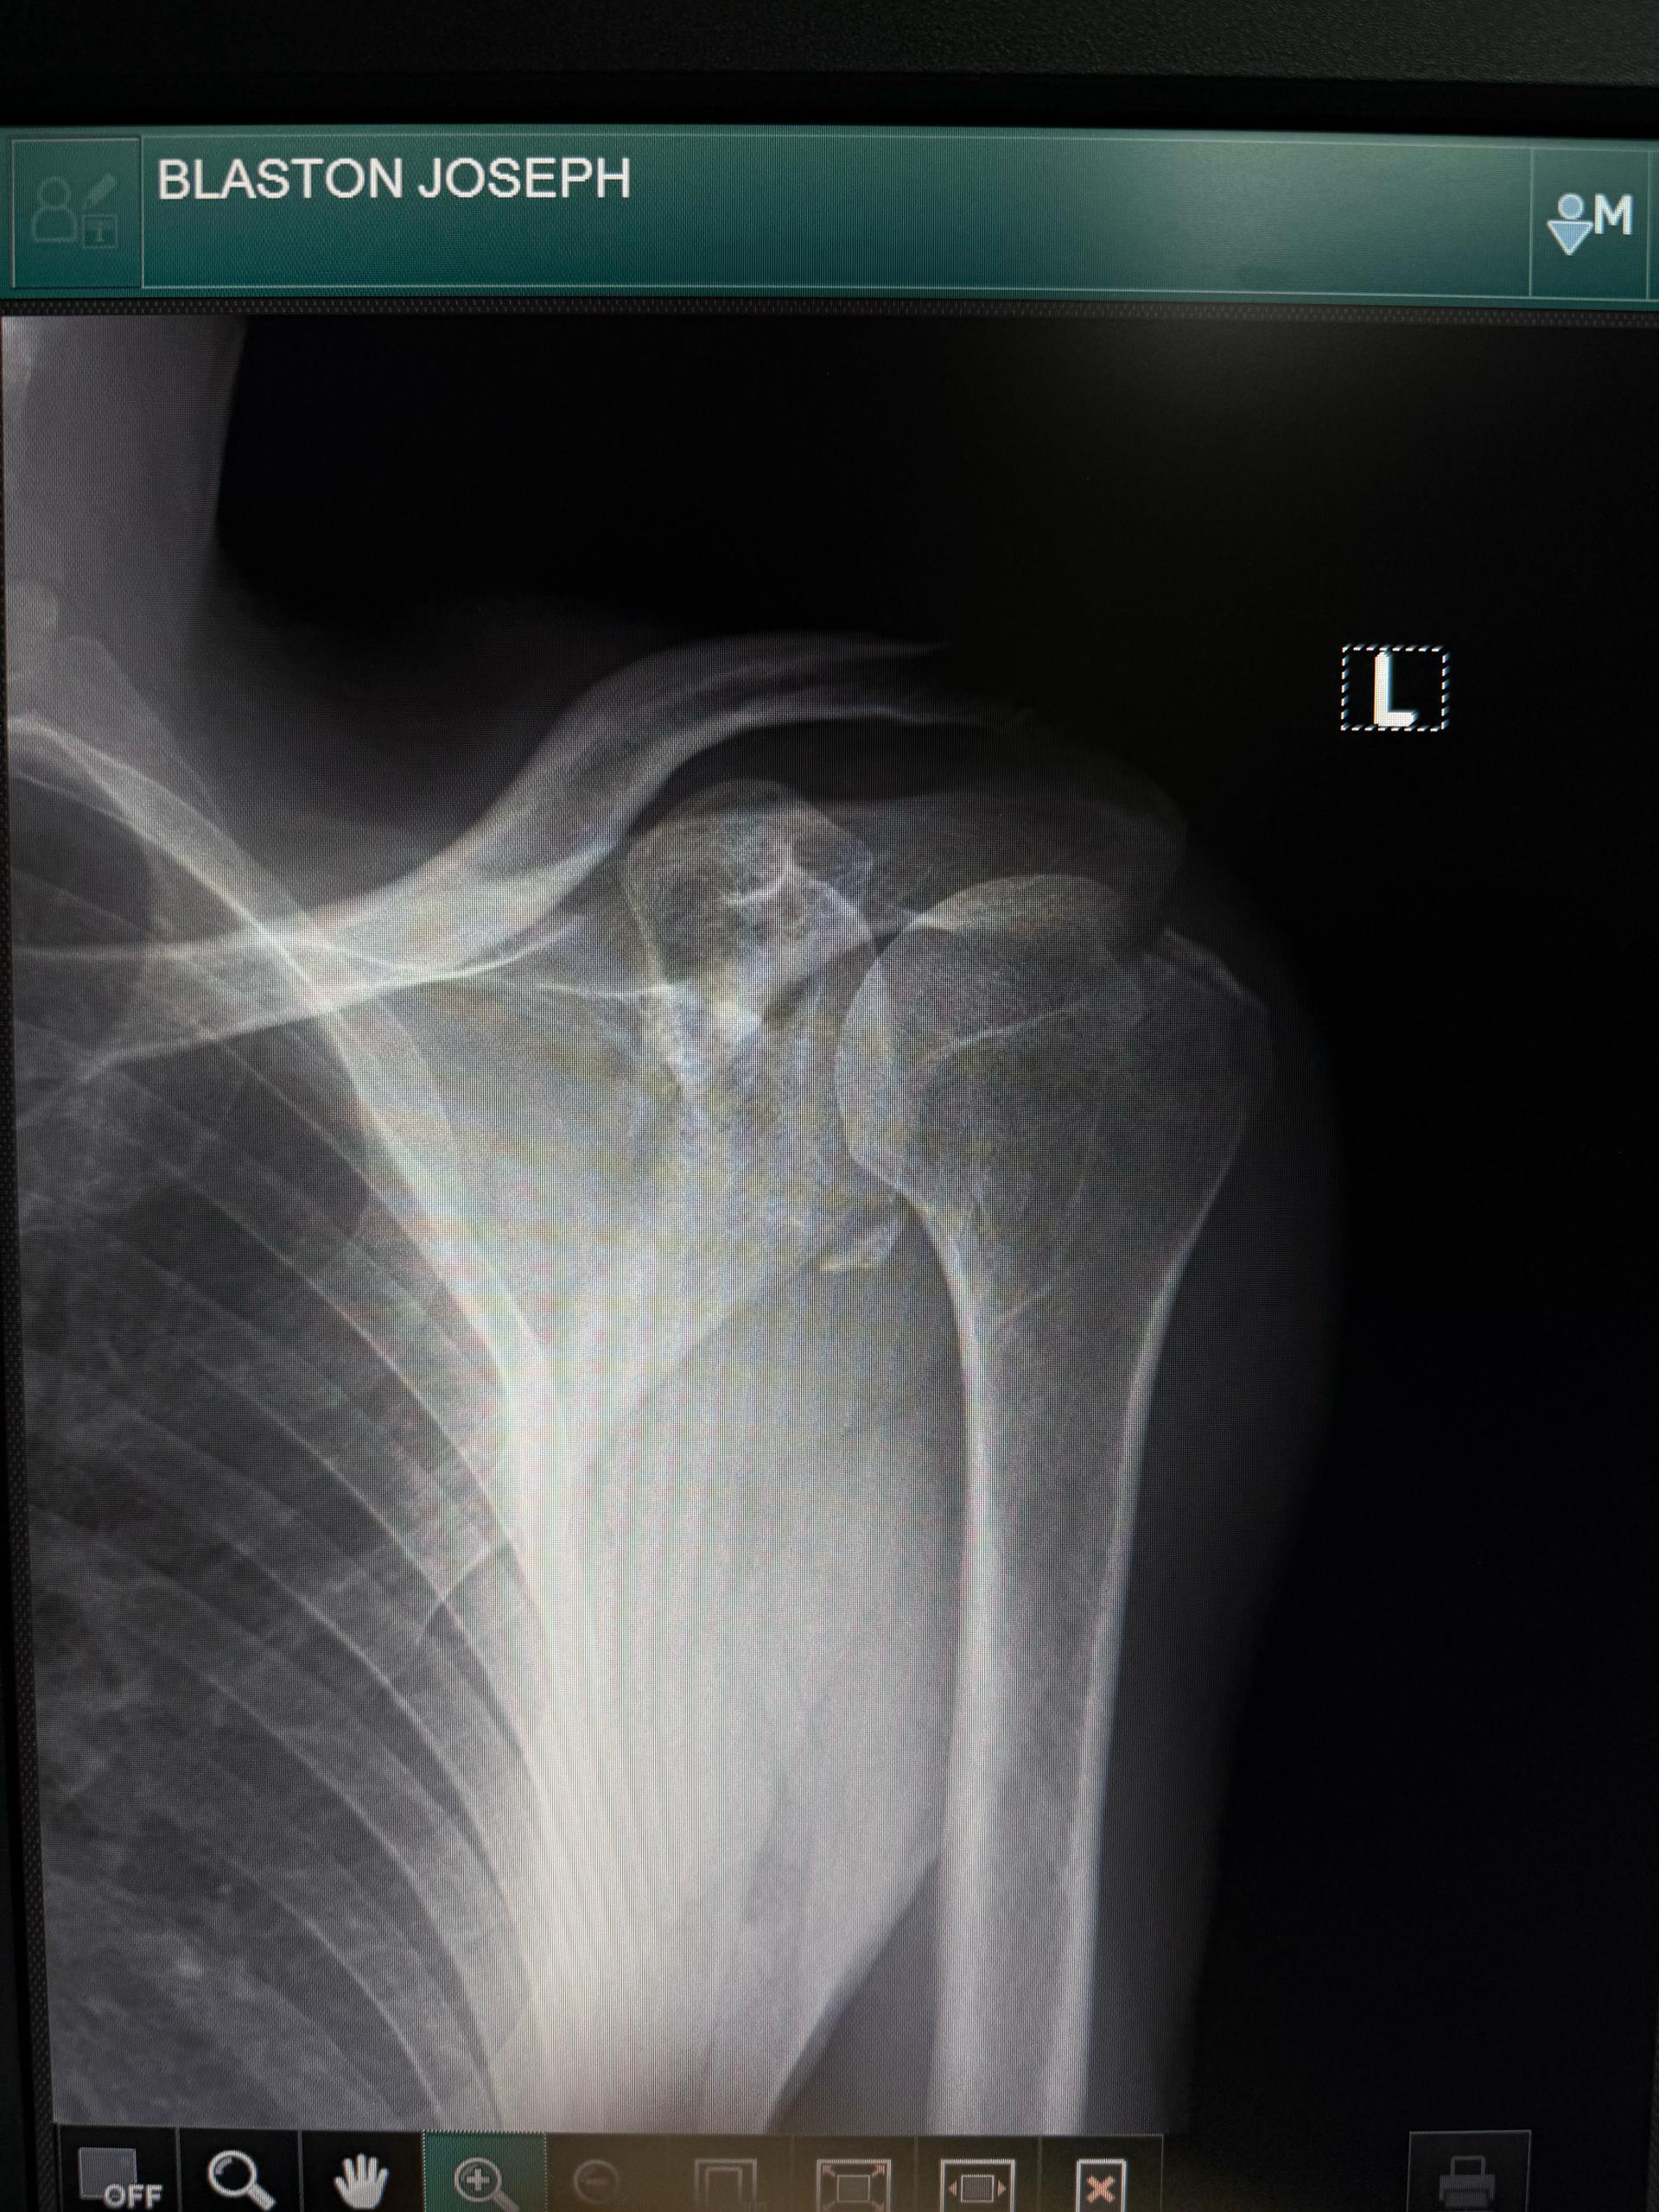

They found an english speaking travel guide who sat with me all night and when they put my arm back in my socket and he was able to translate that the doctors were sorry they did it without any pain medication. Because I had a drip in, they thought the nurse had already given it to me. The nurse thought that the doctors would do it. He also got hold of my daughters in Australia on a video call which was great. Although I was in a lot of pain it was nice to see them and show them I was okay (apparently thats not how it appeared to them). He took the photos of my before and after Xrays to show the doctors because that’s how it works over here. My arm felt much better back in it’s socket and not pressing against my ribs. And I am sure it was great entertainment for the dozens of people in the room with me.